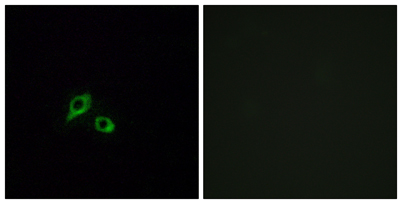

Dilutions: Western Blot: 1/500 - 1/2000. Immunohistochemistry: 1/100 - 1/300. Immunofluorescence: 1/200 - 1/1000. ELISA: 1/20000. Not yet tested in other applications.

Cellular localization: Cell membrane; Multi-pass membrane protein.